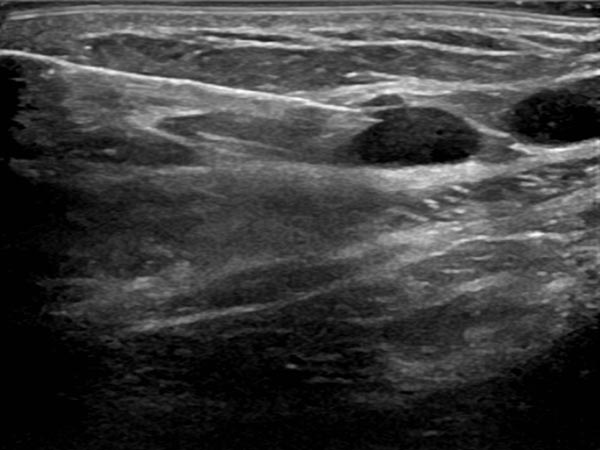

Ultraschall der Bauchwand, etwas weiter kaudal. Hier sind die zystischen Anteile der Lymphatischen Malformation kleiner. Die Läsion liegt jedoch weiterhin extraperitoneal.